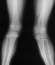

X-ray Set 1. 10 Months post Fracture, Right 8* Left 19* Mechanical axis